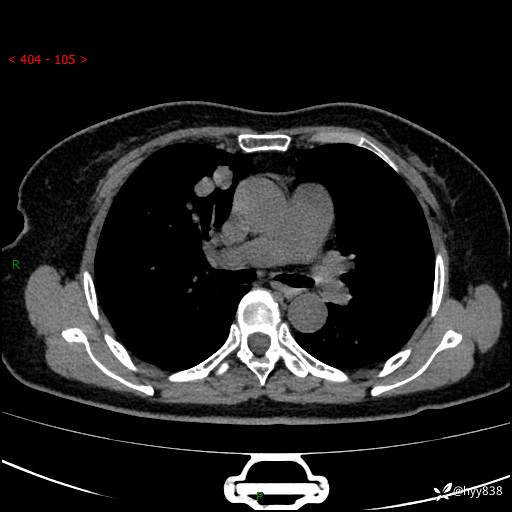

70岁/女,发现右上肺肿物10天。患者过敏体质,只有平扫,错过了一定可惜---结果公布~

【患者信息】:70岁/女

【主诉】:发现右上肺肿物10天

【现病史及既往史】:者10天前因“背部酸痛”于当地治疗,无发热,无呕吐,无头痛头晕等不适,胸部CT示右上肺肿物。遂来我科就诊,门诊看过病人后以“”收入我科, 自患病以来,精神、饮食、睡眠尚可,大小便正常,体力体重无明显减轻。

【检查】:胸部CT平扫(患者过敏体质,不能增强)